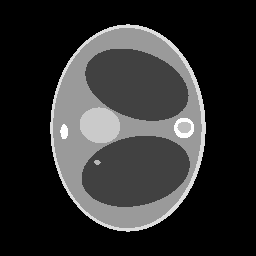

We assume to measure a total of photons and compute synthetic data from eq. 11 for a phantom electron density modeling a transversal slice of a human thorax. The phantom (see fig. 2(b)) consists of characteristic functions of ellipses of different sizes and opacities and is a modified version of an earlier phantom which was used in [12]. It is 28.4 cm resp. 21.3 cm wide at its largest and smallest diameters and its gray values are chosen as electron densities of materials typical in a human thorax [15, 3, 30].

In the reconstruction, a suitable choice for the regularization parameter is computed by the L-curve method. In fig. 3(e) we see that a reconstruction of the electron density from works well and the TV penalty term reduces the effects from the Poisson noise sufficiently. However, adding the component (fig. 3(f)) to the spectrum distorts the reconstruction. Due to the enormous noise level brought into the model by the component , the TV-regularized solution suffers from bad quality. Details are less visible or harder to localize and intensities of the different regions are altered complicating material recognition.

The method is tested for two synthetic phantoms; firstly, the thorax phantom already used in section 2. Figure 8 shows how the algorithm succeeds in decreasing the impact of the higher-order scattering. The ground truth is displayed in fig. 8(a). Expectably, the CT reconstruction (fig. 8(d)) is not accurate enough, but can be used as a prior to estimate the nonlinear weight function . Using , the CST reconstruction is computed. For comparison, we give both the solution of eq. 25 (without ) and eq. 26 (with ). As in section 2, eq. 25 cannot yield a useful reconstruction. The minimizer when is the Kullback-Leibler divergence (13) and is very noisy (fig. 8(b)) and using TV regularization, some noise can be filtered out, but only at the cost of losing small details of lower contrast (fig. 8(e)). As desired, applying to the data reduces the noise level, see fig. 8(c) and fig. 8(f) (with TV regularization). After applying , we use the norm as data fidelity measure. Densities and contrasts are accurately recovered and previously vanished details can be correctly located.